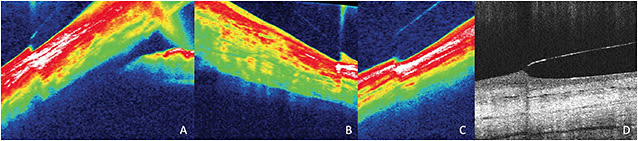

Careful biomicroscopy is mandatory when fitting scleral lenses, but minute findings can evade even the most astute clinicians. AS-OCT can clarify post-settling areas of concern. Lens clearances of 50 microns or less are difficult to observe behind the slit lamp and can be confused with lens touch (Figure 1). Lens awareness can also be difficult to solve (Figure 2). AS-OCT over uncomfortable areas in both primary and extreme gaze can identify whether edge lift, impingement, or poor lens design is to blame (Figure 3).